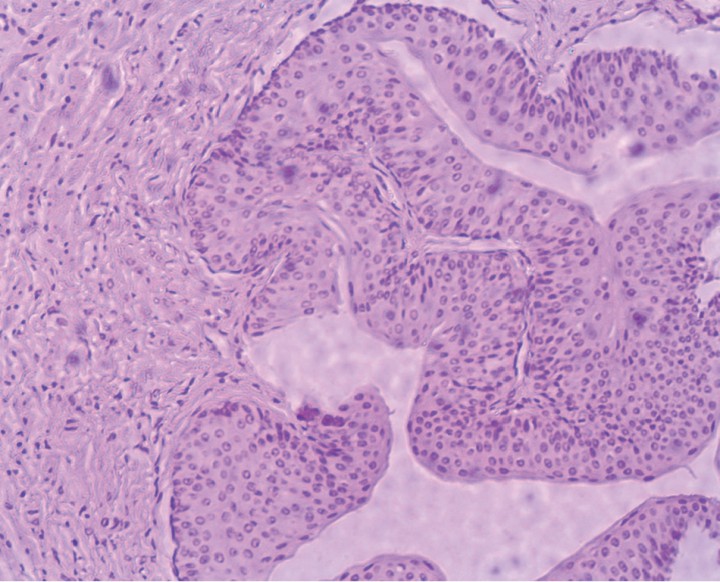

Se realizó una ureteronefrectomía laparoscópica (Fig. 5), así como la histopatología del riñón y uréter. El estudio histopatológico confirmó la hidronefrosis y, en la dilatación quística del uréter, se apreció un adelgazamiento de la pared con hiperplasia de la capa muscular y de su epitelio en la zona de resección. No se observaron cambios neoplásicos ni inflamatorios asociados (Fig. 6).

<p>Imagen histológica del uréter. Se observa una hiperplasia de la capa muscular y del epitelio transicional de revestimiento en la zona de resección. Tinción de Hematoxilina-Eosina (x100).</p>

Imagen histológica del uréter. Se observa una hiperplasia de la capa muscular y del epitelio transicional de revestimiento en la zona de resección. Tinción de Hematoxilina-Eosina (x100).

El diagnóstico de estenosis ureteral se realiza, idealmente, con hallazgos histopatológicos asociados con el estrechamiento de la luz ureteral. Los hallazgos histopatológicos de la estenosis ureteral en el gato incluyen tejido de granulación mural con alteración de las células epiteliales, ureteritis con fibrosis e inflamación, e hipertrofia de la capa muscular.[ Lee N, Choi M, Keh S et al. Bilateral congenital ureteral strictures in a young cat. Can Vet J. 2014; 55(9): 841 - 844. [PubMed] ]